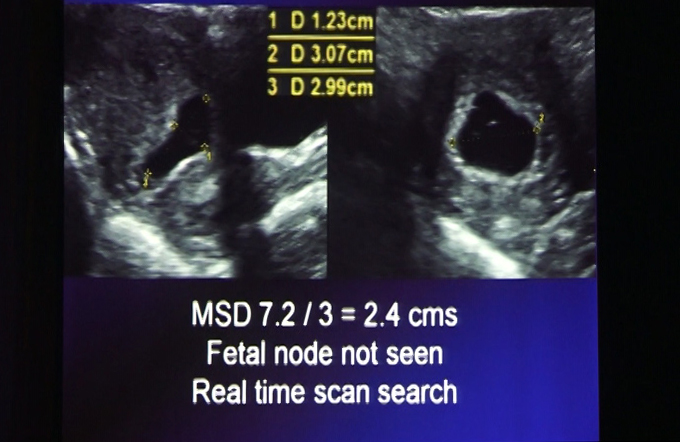

Ultrasound(On Crown Rump Length) - Part VIII